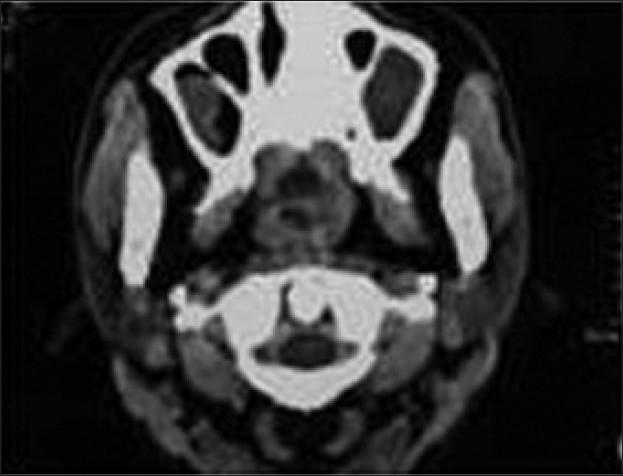

复发性鼻硬结病罕见病例的气道管理

Airway management of an unusual case of recurrent rhinoscleroma.

Rhinoscleroma is a rare entity encountered in anesthesia practice. We discuss the management of a patient after its recurrence, involving the upper respiratory tract i.e. nasopharynx and oropharynx, which compromised the airway. The pateint was referred for anesthesia on three different occasions with different presentations owing to the recurrence of symptoms.The presence of an oropharyngeal membrane with a small opening made airway management a challenge. The patient was successfully managed on all three occasions. Imaging facilitated assessment and subsequent airway management.

摘要

鼻硬结病是麻醉实践中遇到的一种罕见病症。我们讨论了一名患者复发后涉及上呼吸道即鼻咽和口咽的处理情况,这对上呼吸道造成了损害。由于症状复发,该患者在三个不同场合因不同表现被转诊接受麻醉。口咽膜存在且有一个小开口使得气道管理成为一项挑战。该患者在所有三次场合均得到了成功处理。影像学检查有助于评估及后续的气道管理。